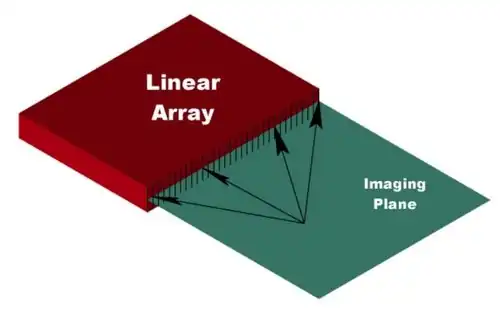

Linear array

Linear transducer arrays (both curved and straight) are commonly used in conventional medical ultrasound. They are available in a wide variety of sizes and shapes.[2] They are easily adapted for use in thermoacoustic imaging. Figure 7 illustrates how a linear array is used for 2D thermoacoustic imaging. The array consists of a number of elements (64 - 256) that are focused in the vertical dimension to maintain maximum sensitivity within a 2D plane extending outward from the front face of the array. Thermoacoustic signals within the plane are localized by calculating the times-of-flight from each position within the plane to each element of the array (arrows, Fig. 7).[20][3]